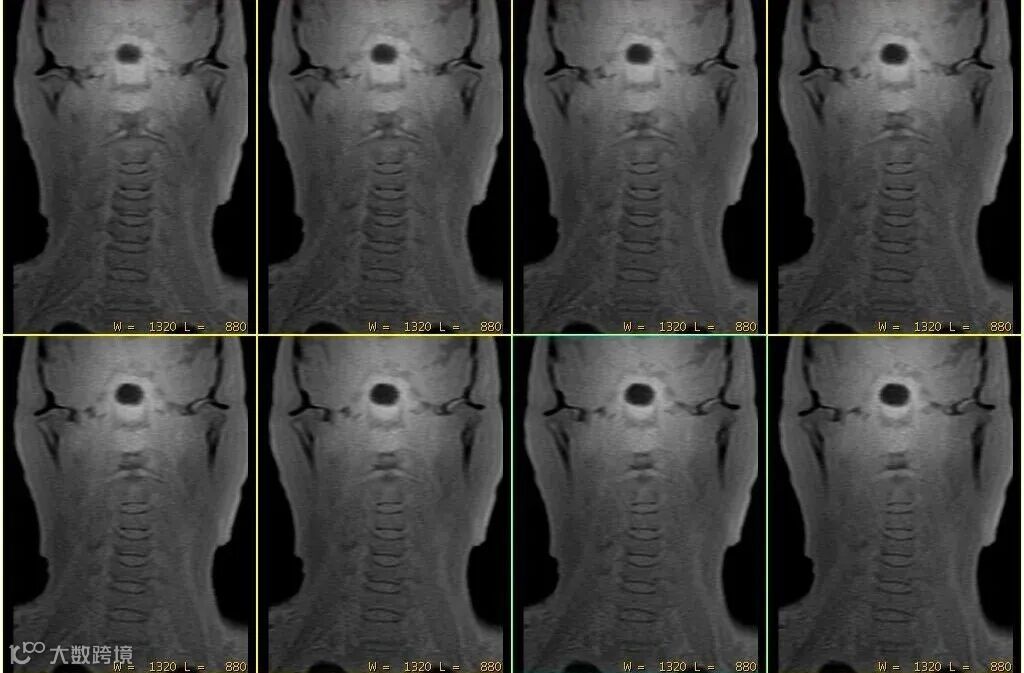

其原始对比度主要反映组织的质子密度和T1弛豫特性。上图△,FA=1°,体素0.8*0.8*0.8mm。

经过从黑到白的灰度反转后,能产生与X线片或CT极为相似的对比度,从而实现直观的“类CT”视觉效果。

上图△,椎体成像。成像FA =2°,体素1.2*1.2*1.2mm。